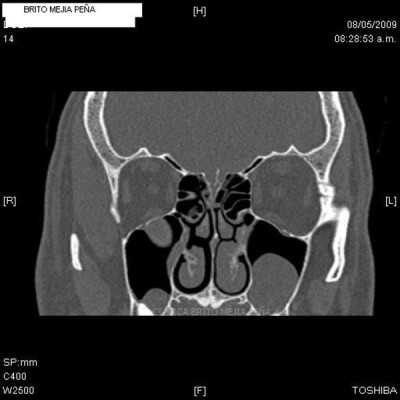

Cabeza y Cuello 2

Envíado por BMP Imágenes Diagnósticas

BMP Imágenes Diagnósticas